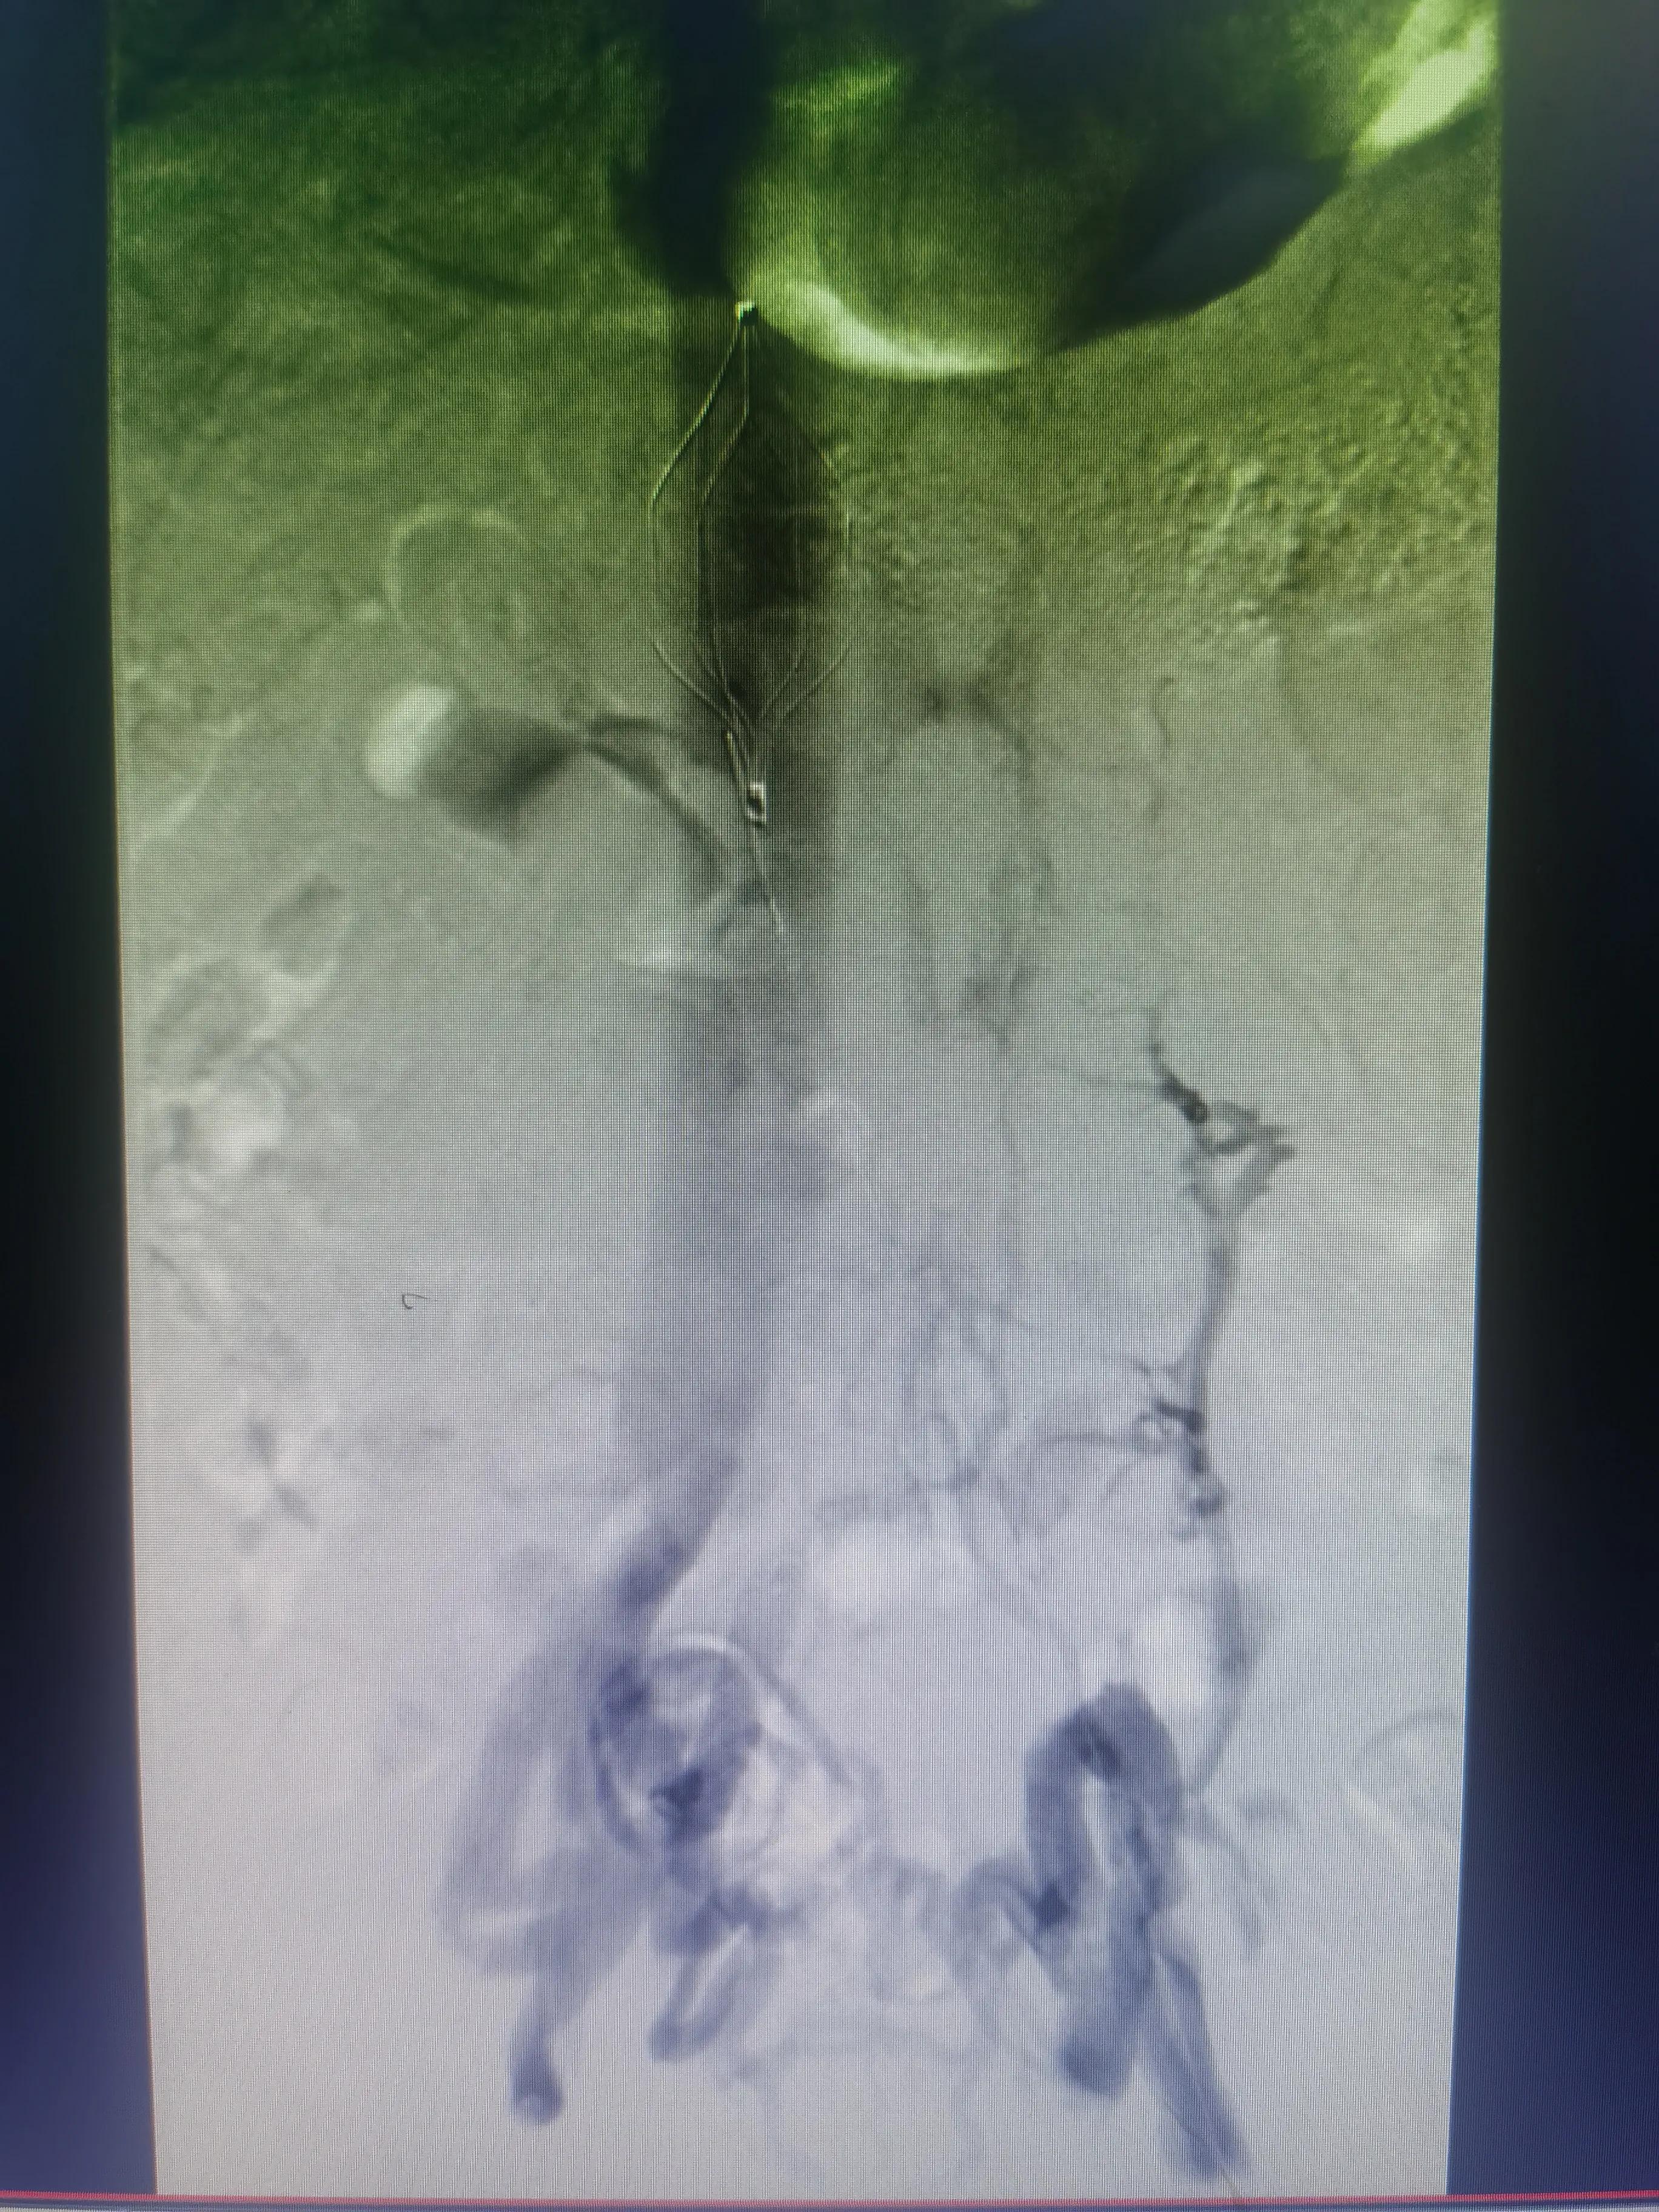

答:这个就需要根据患者自身情况制定个性化治疗策略,主要策略为:①保守抗凝治疗:②系统溶栓治疗;③导管接触性溶栓治疗;④机械性血栓清楚治疗;⑤必要时球囊扩张和支架植入治疗;⑥急危重症病人需切开取栓治疗等。

下腔静脉滤器网住血栓